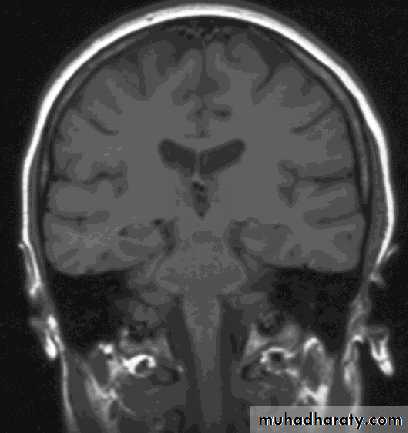

Magnetic Resonance Imaging (MRI)Magnetic Resonance Imaging (MRI)

Uses non-ionizing radiation and has no demonstrated adverse biological effects.Magnetic resonance images can be obtained in any tissue plane

transverse

sagitttalcoronal

ComparisonsMRI image

CAT image

head

Compare bone and soft tissue density